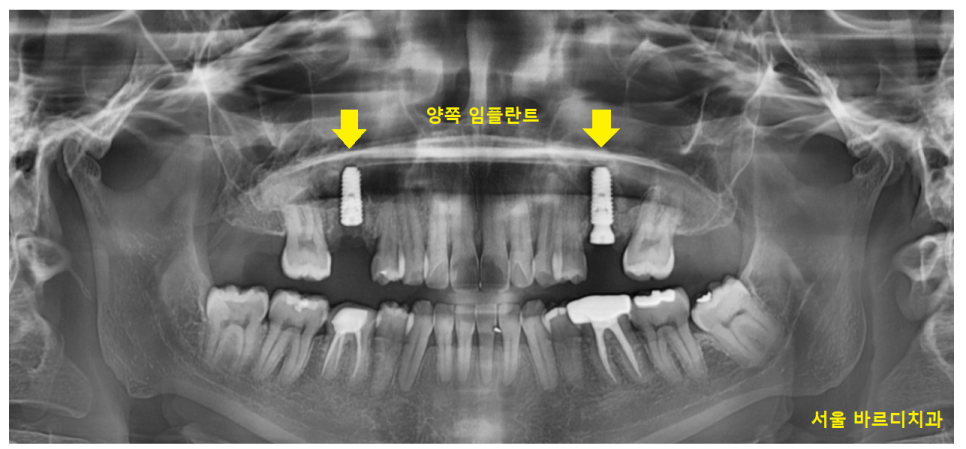

윗니 어금니의 경우 양쪽 모두

충치가 진행되어 뿌리만 남을정도로 썩었습니다.

23.12.30

오른쪽 어금니의 경우

위 아래 모두 문제였지만

임플란트 양쪽 치료가 필요했습니다.

윗니 어금니의 경우 상악동이라는 구조물이 있는데

남아있는 잇몸뼈가 없는 경우

이 상악동을 들어 올려 뼈이식을 진행하여야합니다.

환자분도 2mm 정도 남아 있어서

(일반적으로 임플란트는 8mm정도 필요합니다)